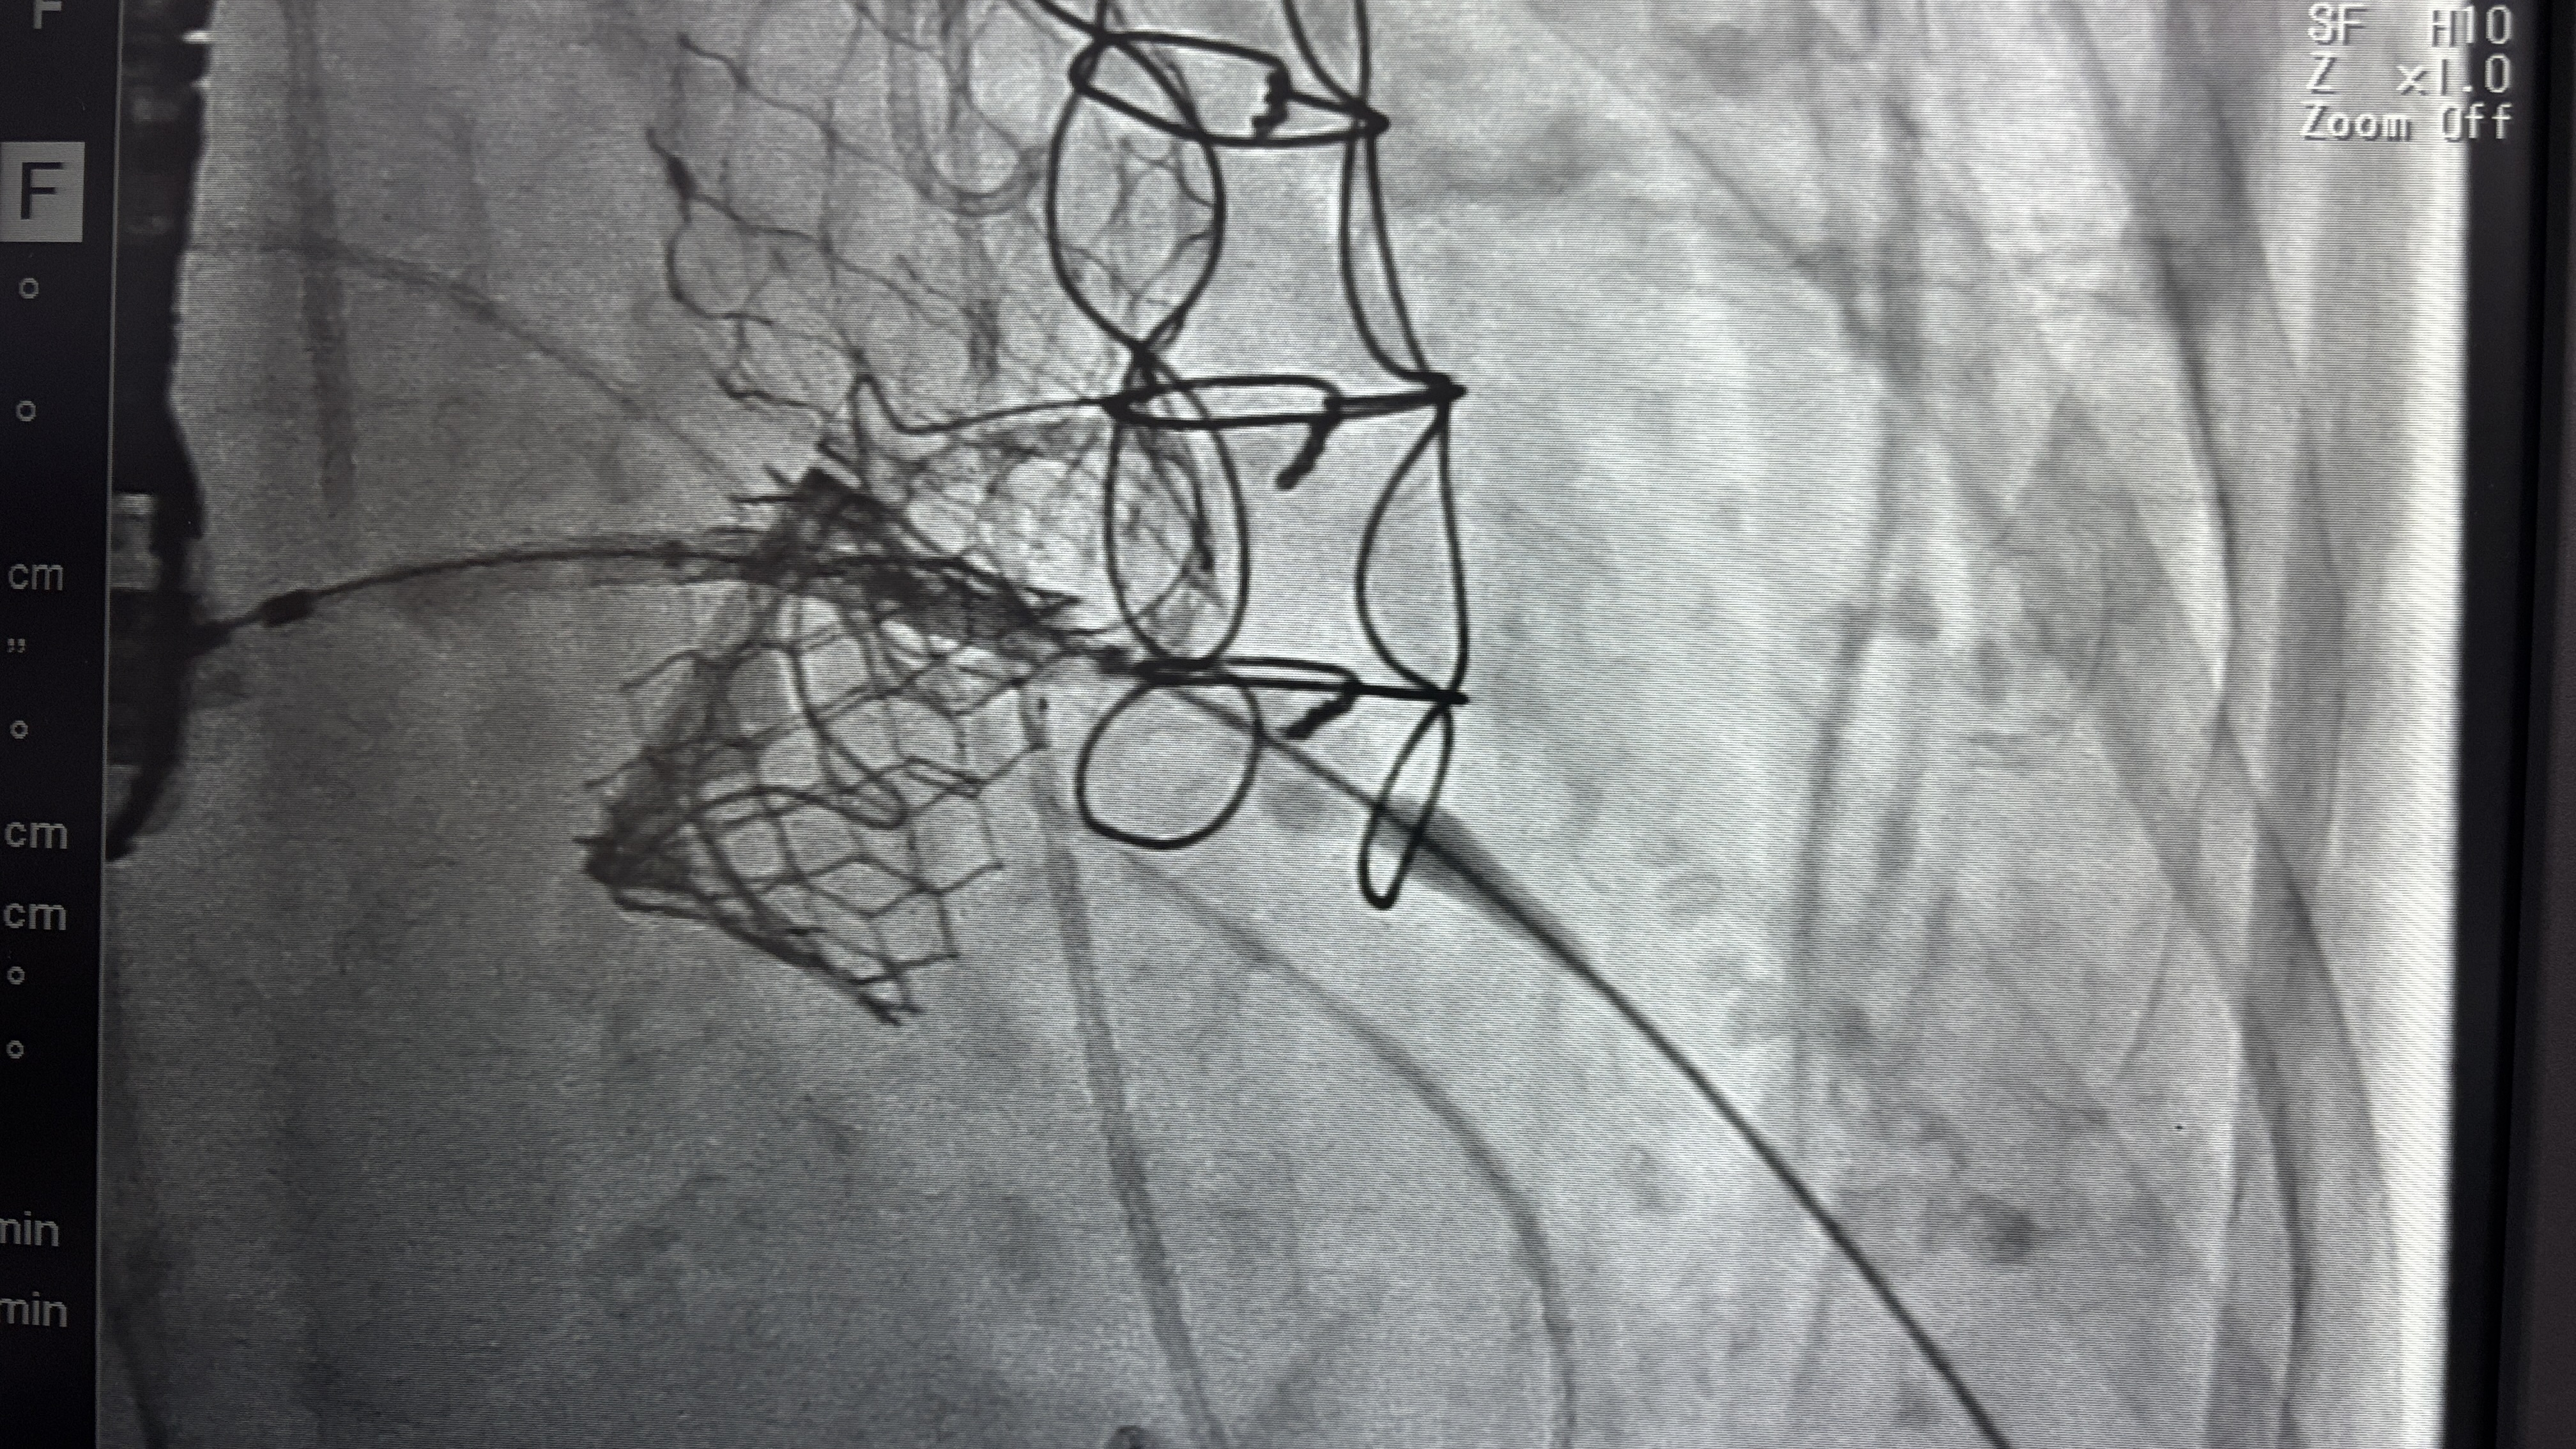

下午繼續幫老闆關胸,準備迎接今天的重頭戲——Aortic valve in valve 與 Mitral valve in valve

今天請北榮的宋大師下來指導,老闆、邱醫師其實都已經是箇中好手,高手過招,更讓我嘆為觀止,不知道什麼時候才能練成他們那樣